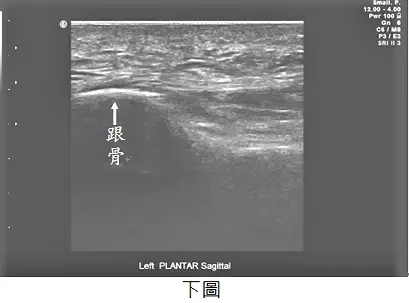

63歲女性病人,主訴右足底疼痛,於起床著地時特別明顯。超音波檢查如圖,上圖為右側足底筋膜連結至跟骨處,下圖為左側足底筋膜連結至跟骨處,最可能診斷為何? 圖片描述 圖片描述

關鍵在於利用musculoskeletal ultrasound評估近側足底筋膜(plantar fascia)於跟骨(calcaneus)附著處的厚度與回聲特性,診斷足底筋膜炎(plantar fasciitis)。

超音波上圖(右足)可見足底筋膜在跟骨附著處增厚,測得厚度約0.55 cm(5.5 mm),且筋膜呈低回聲(hypoechoic),纖維結構不均;下圖(左足)同部位筋膜厚度明顯較薄(約3 mm以下)、高回聲且纖維排列均勻。病側筋膜增厚超過正常上限,並伴有水腫樣回聲改變,為plantar fasciitis典型所見 (journals.lww.com)。